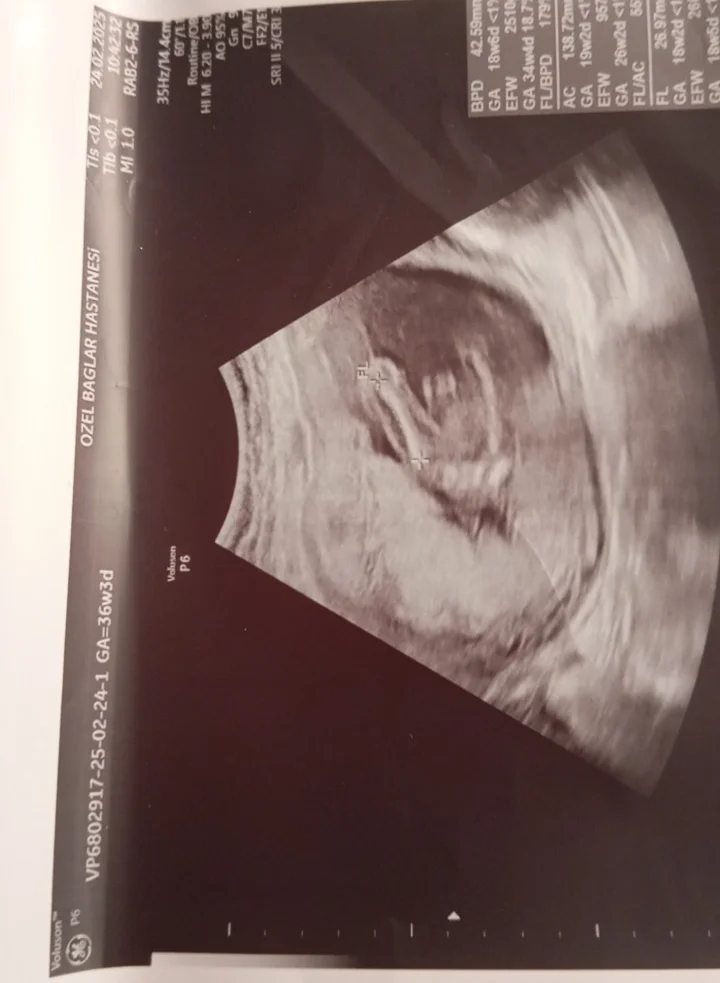

Erkek hissettimKızlar 10 haftalık hamileyim cinsiyet tahmini sizce nedir

Erkekmiş

Hayırlı olsun canımErkekmiş